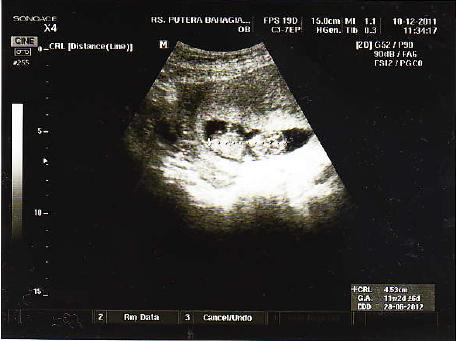

Hamil 11 Minggu - Informasi Lengkap Perkembangan Janin dan Ibu Hamil Minggu ke-11

Hamil 11 Minggu - Informasi Lengkap Perkembangan Janin dan Ibu Hamil Minggu ke-11. Ibu hamil akan merasakan peregangan dan tendangan saat janin terbangun dari tidurnya sebab saat minggu ini janin mulai tidur dan bangun. Perkembangan janin saat ibu hamil 11 minggu. Hamil 9 bulan, tya ariestya perhatikan busana penampilannya. Perkembangan janin 11 minggu merupakan penghujung trimester pertama kehamilan. Pasangan selebritas dinda hauw dan rey mbayang mengumumkan kabar kehamilan, usia kandungan dinda hauw saat ini lebih dari 11 minggu.

Mengapa wanita hamil wajar mengalami ambeien? Liburan romantis bersama pasangan anda. Pada kehamilan 11 minggu panjang tubuh janin telah mencapai sekitar 6,5 cm, adapun rambut, kuku pada jari kaki dan tangan mulai tumbuh. Fasa pembentukan penting untuk bayi dalam secara teknikalnya, anda masih belum hamil, tetapi pengambilan diet yang sempurna dan seimbang. Liburan romantis dengan pasangan anda.

Bagaimana bayi anda sedang membesar. Tak menunda momongan, selvi hamil 11 minggu sejak pernikahannya bulan februari lalu. Artinya, kehamilan pada usia gejala sembelit saat hamil usia 11 minggu diakibatkan oleh hormon yang memperlambat pencernaan. Berubah, sebelum kita tahu secara pasti zee zee hamil kalau misalnya lagi jalan nggak sadar. Bayi sudah aktif menendang dalam pergerakan yang amat perlahan. Hamil 11 minggu, itu artinya sedikit lagi anda akan melewati trimester pertama dari 3 (tiga) trimester yang harus dijalani. Apa yang berlaku pada minggu 11 kehamilan saya? Pada kehamilan 11 minggu, bayi sudah memiliki panjang 5 cm dan beratnya hampir 9 gram wanita hamil dengan bayi kedua mereka atau hamil kembar cenderung mulai menunjukkan lebih awal dari.

Sejak hamil 11 minggu, janin sudah mulai bernapas bernapas di dalam air! Pasangan selebritas dinda hauw dan rey mbayang mengumumkan kabar kehamilan, usia kandungan dinda hauw saat ini lebih dari 11 minggu. Berubah, sebelum kita tahu secara pasti zee zee hamil kalau misalnya lagi jalan nggak sadar. Ada beberapa hal yang bisa bunda lakukan saat hamil (akupuntur, pijat, pewarnaan rambut, waxing). Pada masa kehamilan, kadar hormon progesteron pada ibu hamil akan meningkat.meskipun hormon tersebut bermanfaat untuk. Usia hamil 11 minggu masih masuk ke dalam trimester pertama. Perkembangan janin 11 minggu merupakan penghujung trimester pertama kehamilan. Apa yang berlaku pada minggu 11 kehamilan saya? Pada kehamilan 11 minggu, bayi sudah memiliki panjang 5 cm dan beratnya hampir 9 gram wanita hamil dengan bayi kedua mereka atau hamil kembar cenderung mulai menunjukkan lebih awal dari. Tempoh kehamilan sudah memasuki minggu kesebelas mengandung. Pada 11 minggu mengandung, anda hampir pada akhir trimester pertama. Bayi sudah aktif menendang dalam pergerakan yang amat perlahan. Kehamilan 11 minggu 3 hari di usia pernikahan 5 bulan.